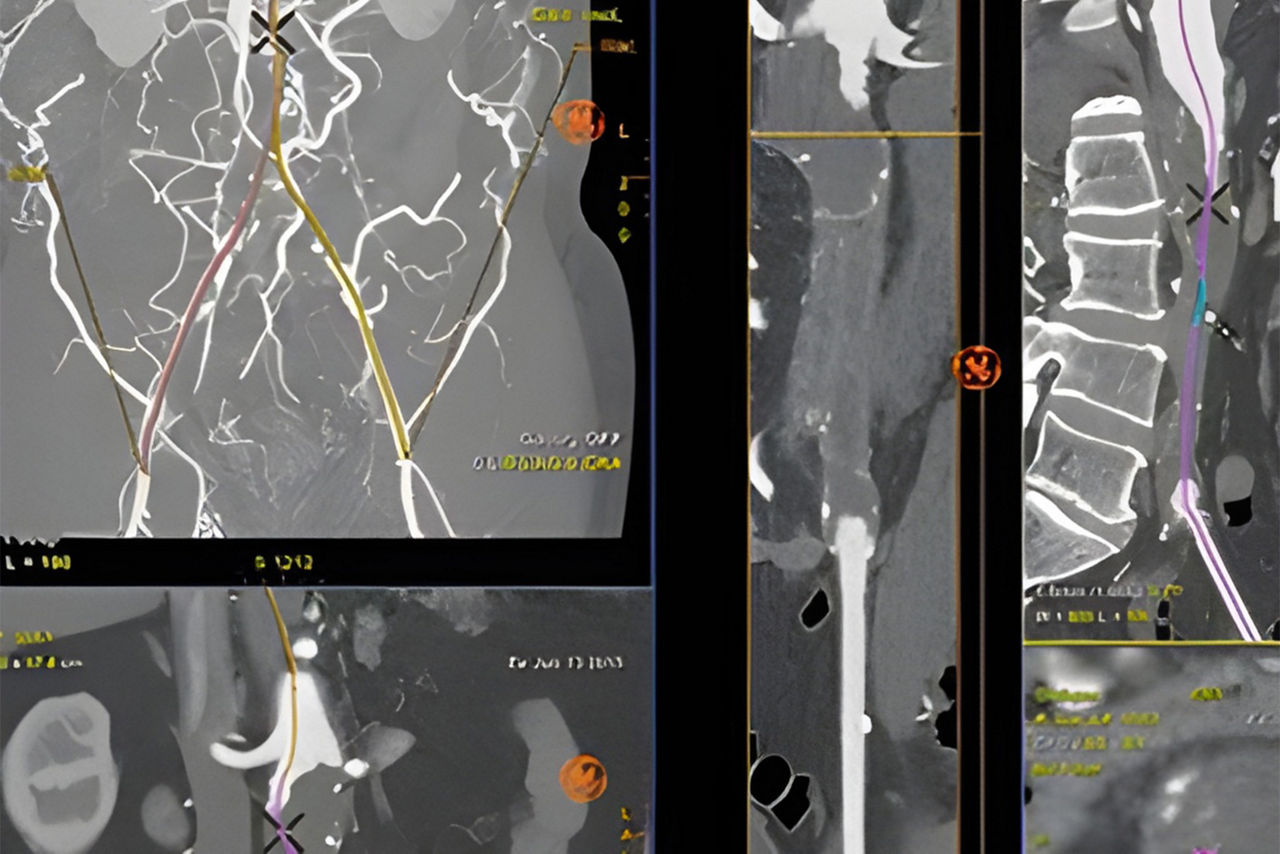

Vessel ASSIST delivers accurate and easy anatomy segmentation and accurate vessel quantification from 3D volumes. It also offers advanced 3D roadmap and augmented image guidance capabilities to guide catheter with confidence.

Plan

Automatically extract the bone and vessel anatomies. Edit vessel centerlines and bridge them through occlusions.

Guide

Select from the sub-volumes of vessels, centerlines, calcifications and landmarks to overlay on live fluoroscopy for 3D fusion guidance, with digital zoom, to guide recanalization.